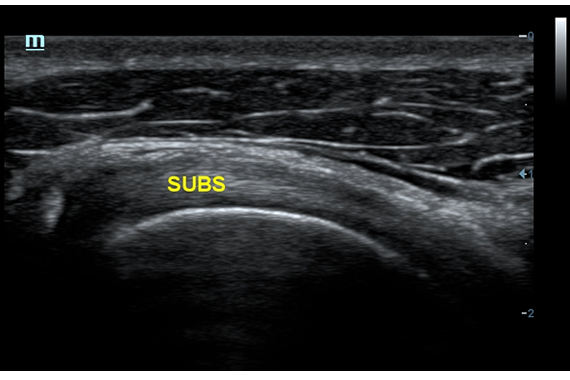

• Small parts package - предустановленные параметры, аннотации, маркеры, программы измерений для исследования малых (поверхностных) органов

• Линейный ультразвуковой датчик Mindray 7L4A